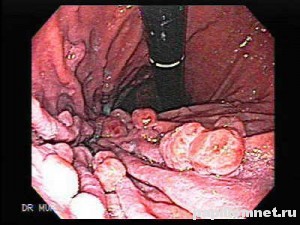

Снимок полипа в области пищевода

Одним из серьезных заболеваний верхних отделов пищеварительной системы является полип пищевода. Он имеет свойство развиваться бессимптомно, поэтому ранняя диагностика заболевания существенно затруднена. Начальные симптомы заболевания проявляются незначительно, не вызывая особых беспокойств, пока опухоль не достигнет больших размеров. Прогрессирующий полип характеризуется болезненностью за грудиной и затруднениями при глотании пищи. При бесконтрольном росте новообразования могут достигать гигантских размеров, существенно ухудшая качество жизни больного. Симптомы растущего полипа в числе прочих проявляются затруднением глотания. На поздних стадиях больной вообще не может проглотить плотную пищу, и для поддержания самостоятельного питания ему назначается специальная диета.